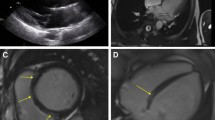

This observation is consistent with the growing body of evidence highlighting the predictive value of LGE for Co-VAs and SCD in MVP patients [8,9,10, 14, 16, 17, 21]. Indeed, higher extension of low voltages has been found in electrophysiological studies in the case of LGE involving papillary muscle and lateral/infero-lateral LV wall (in patients with MVP and complex arrhythmia, supporting the role of fibrosis as electrophysiological substrate [22].

Myocardial fibrosis in MVP seems to be the result of increased traction of the papillary muscles and mechanical stretch of the surrounding myocardium. LGE thus mainly involves the inferior and lateral basal wall of the LV, with a non-ischemic appearance (mid-wall or patchy) and less frequently with subendocardial pattern and the posteromedial papillary muscle [23]. Moreover, systolic curling of the mid-basal lateral wall may constitute a potential electromechanical trigger further enhancing the risk of VA [23].

Importantly, despite strong association with Co-VAs, a non-negligible proportion of events occurred also among patients without LGE, suggesting the multifactorial etiology of arrhythmias and supporting the need for further research to achieve a multiparametric risk stratification. Of note, interstitial fibrosis detected only by mapping techniques may partly explain this discrepancy. Indeed, increased native T1 and ECV values on the lateral wall in patients with MVP were associated with arrhythmic events even in the absence of LGE [15, 25]. However, we could not meta-analyze T1 mapping due to the limited study number available. Future studies will elucidate the addictive performance of these promising markers over LGE among MVP patients.

The analysis also supported the role of MAD in predicting arrhythmic risk. Although the presence of MAD showed a moderate association with co-VAs (log OR 0.95), with relatively high sensitivity (0.77) and negative likelihood ratio (1.3), the predictive value of MAD appears to be lower than that of LGE. Its low specificity (0.43) may indeed be related to the dichotomic evaluation of MAD rather than an evaluation based on MAD extension and site. In fact, a degree of MAD seems to be prevalent in the general population, possibly representing a normal variant of mitral annulus anatomy [26]. Conversely, MAD extension over a certain length, especially in the setting of MVP, resulted associated with Co-VAs and SCD, with pathological MAD reported for length higher than 5 mm or 8.5 mm [9, 27], albeit a precise cut-off that remains to be determined, and when localized in the infero-lateral wall and associated with MVP [9, 23, 26]. Associated with MVP, longer MAD seems to worsen mitral annulus dynamics with subsequent more severe mechanical wall stretch and fibrosis, concurring in eliciting arrhythmias.